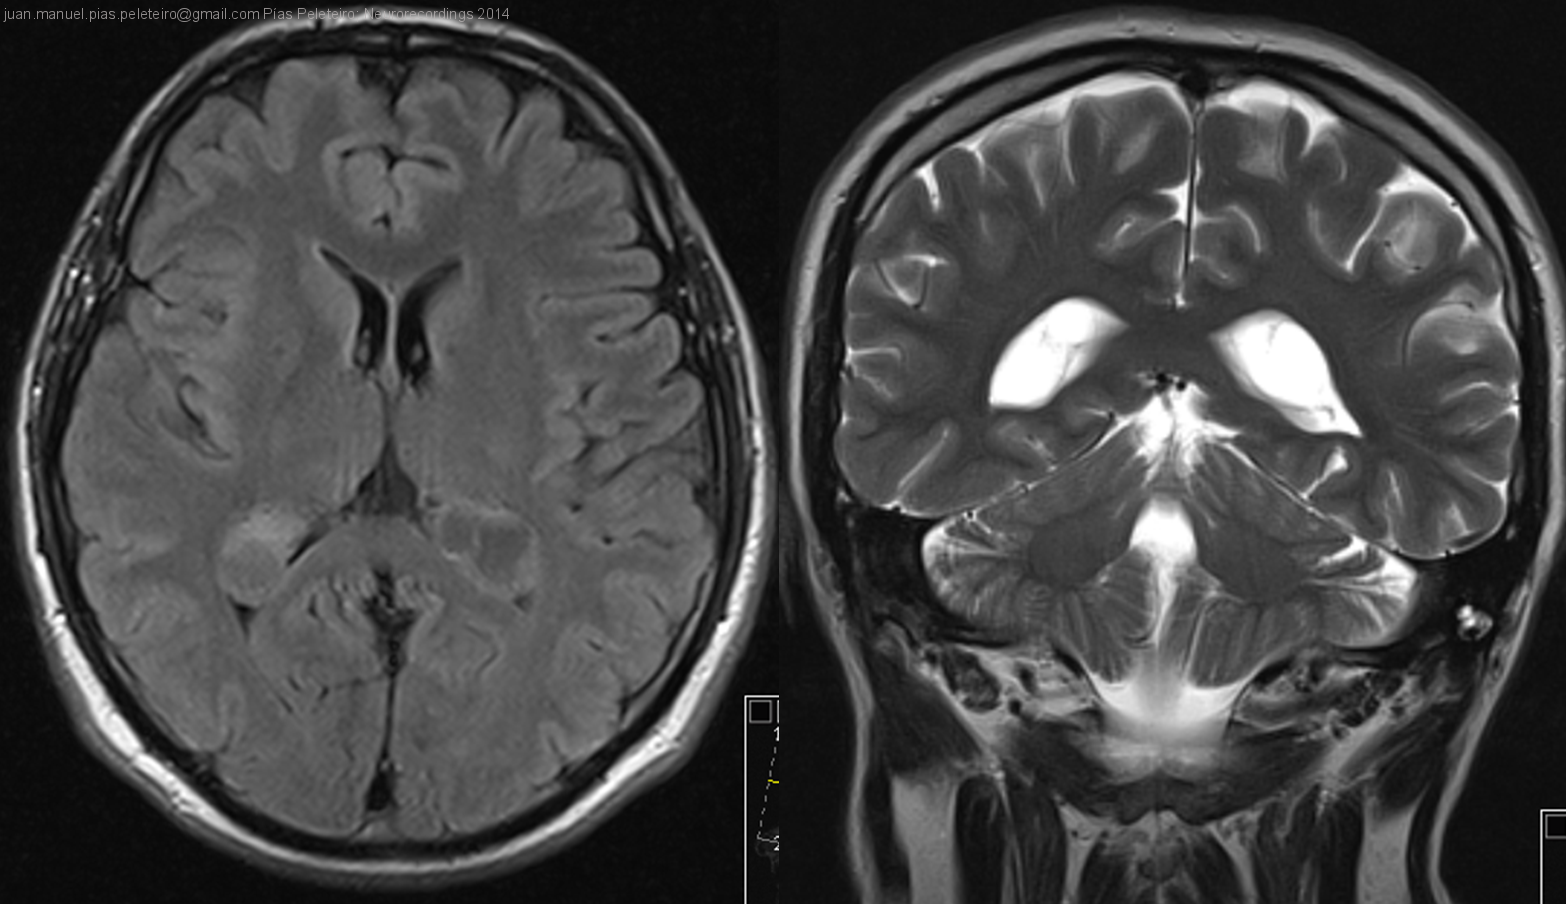

Xantogranulomas de plexos coroideos como hallazgo incidental

Hombre | 40 años

Diagnóstico final: Xantogranulomas de plexos coroideos

Varón de 40 años que acude a la consulta de Neurología por cefalea. Antecedentes personales de hernia de hiato, gastritis crónica antral, rinitis alérgica y asma. No refiere hábitos tóxicos ni alergias medicamentosas. ...